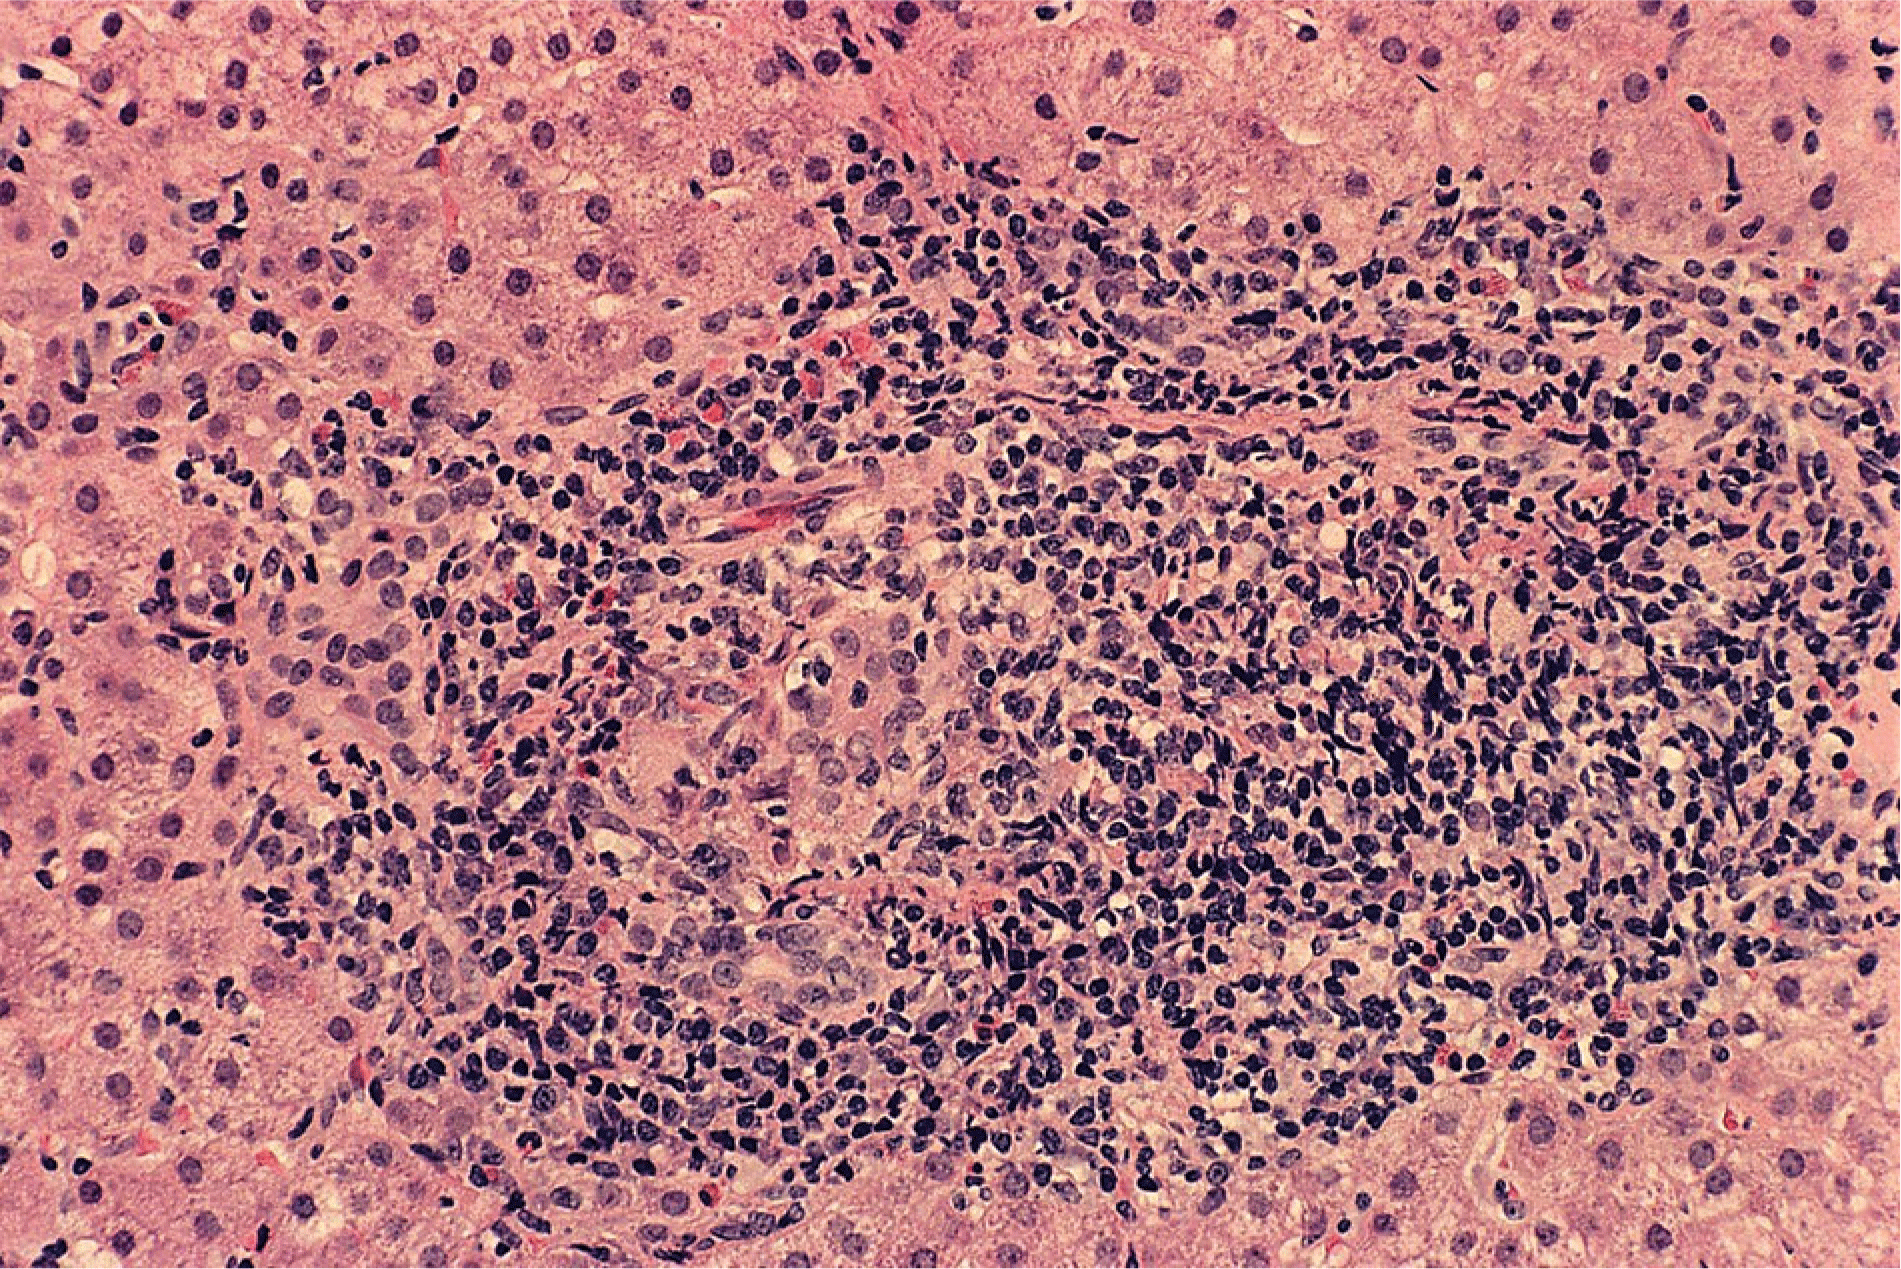

- Clinical judgment and expert interpretation of liver tissue are the principal bases for diagnosing the overlap syndromes, and incompatible manifestations of cholestasis (disproportionate serum AP and GGT elevations, destructive cholangitis or ductopenia in liver tissue) or liver inflammation (disproportionate serum AST and ALT elevations, interface hepatitis, and dense lymphoplasmacytic infiltration in liver tissue) are hallmarks of the diagnosis.